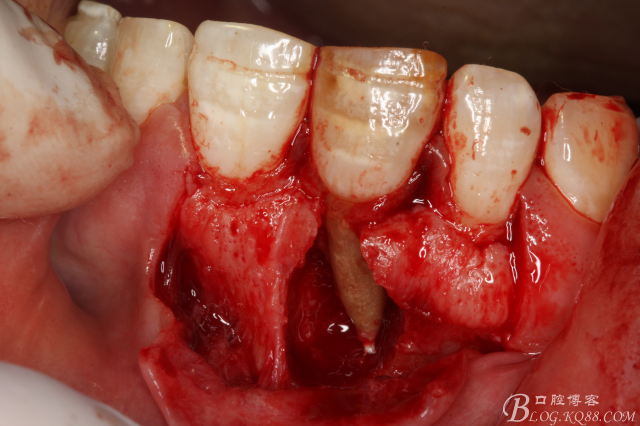

圖6.翻瓣、11唇側(cè)骨壁完全破壞、出乎意料。和根尖片影像資料出入過大。

圖8. 觸目驚心發(fā)現(xiàn)11唇側(cè)骨壁完全缺失,根充超填。預(yù)后難以判斷。